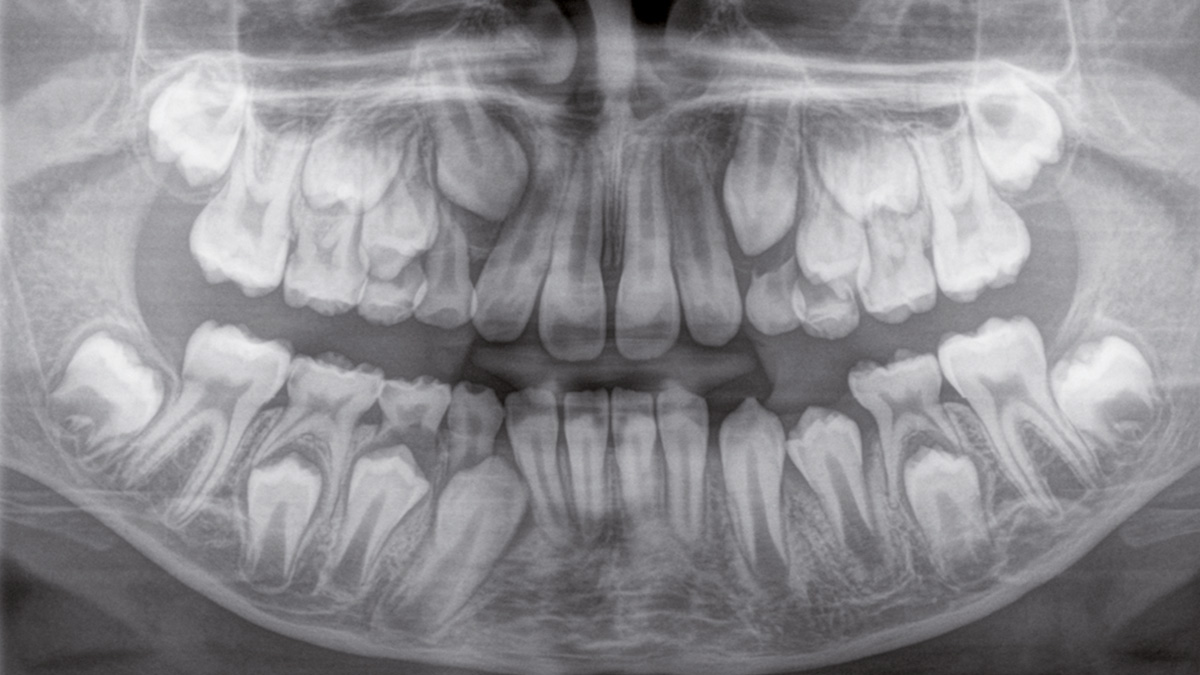

Der 2D/3D Power Performer Orthophos SL ist eine großartige Wahl für alle, die einfach mehr wollen. Der integrierte Direct Conversion Sensor (DCS) wurde für anspruchsvolle Bildqualitätsstandards entwickelt und bietet detaillierte Daten. Der intelligente Autofokus liefert automatisch fokussierte Panoramabilder mit hervorragender Gesamtschärfe. Orthophos SL bietet höchsten Bedienkomfort durch automatische Positionierung, eine anwenderfreundliche, intuitive Bedienung mit dem EasyPad und ein individuell einstellbares Umgebungslicht für ein exklusives Erscheinungsbild.

Der Direct Conversion Sensor erfüllt besonders hohe Standards für die 2D-Bildgebung

Der Autofokus erzeugt aus mehreren tausend Einzelbildern automatisch eine beeindruckende scharfe Panorama-Röntgenaufnahme

Der Direct Conversion Sensor (DCS) hat den Standard der Panorama-Bildgebung neu definiert. Röntgenstrahlen werden direkt in elektrische Signale umgewandelt – im Gegensatz zu herkömmlichen Systemen gibt es keinen Signalverlust durch Lichtumwandlung, was eine verbesserte Bildgebung ermöglicht. Das Ergebnis sind Bilder mit einer sehr hohen Schärfe, selbst bei niedriger Dosis.

Eine Röntgenaufnahme muss sofort diagnostizierbar sein. Der Autofokus hilft dabei erheblich. Orthophos SL erfasst mehrere tausend Einzelbilder in einem Zyklus und erkennt automatisch scharfe Bereiche, um ein gleichmäßig scharfes Gesamtbild zu erzeugen. Der intelligente Autofokus erfordert keine manuellen Arbeitsschritte vor und nach der Erfassung.